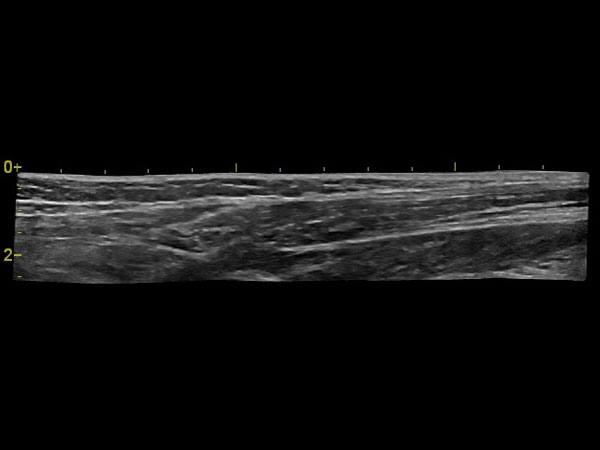

Да